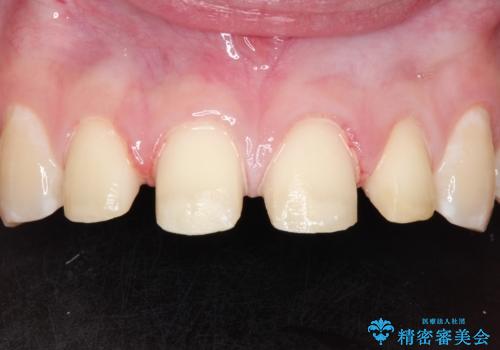

- 前歯をきれいにしたいとのご希望がありました。

生まれつき歯の色が白濁しているところや、黄色くなっているところがあり、セラミッククラウンに審美的改善を行うこととしました。